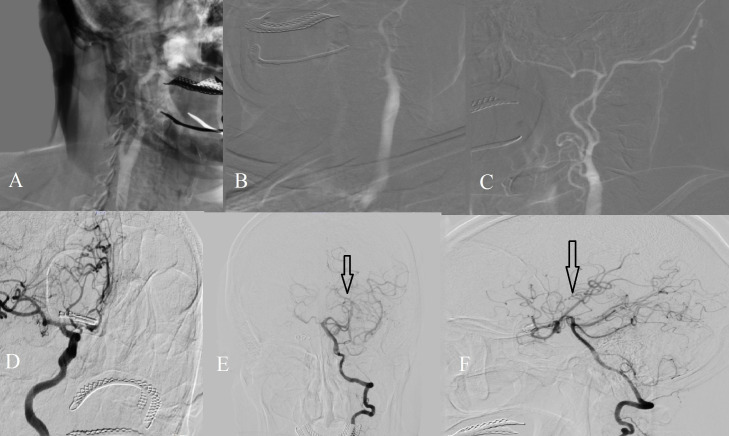

男性,67岁,突发头痛,意识下降,诊断为自发性蛛网膜下腔出血(SAH)。影像学显示前交通动脉(ACoA)动脉瘤和先天性左侧颈内动脉(ICA)缺失,颈动脉管缺失证实了这一点。动脉瘤通过手术切除。术后血管造影显示左侧大脑前动脉和中动脉经后循环侧支血流灌注。病人完全康复了。先天性ICA缺失是罕见的,但显著改变了脑血流动力学,特别是在威利斯周围,使患者易形成动脉瘤。该病例强调了血管成像对SAH患者的重要性,并强调了对先天性血管异常的紧急诊断和干预的必要性。

A 67-year-old male presented with sudden headache and decreased consciousness, diagnosed as spontaneous subarachnoid hemorrhage (SAH). Imaging revealed an anterior communicating artery (ACoA) aneurysm and congenital absence of the left internal carotid artery (ICA), confirmed by the absence of the carotid canal. The aneurysm was surgically clipped. Postoperative angiography demonstrated that the left anterior and middle cerebral arteries were perfused via collateral flow from the posterior circulation. The patient made a full recovery. Congenital ICA absence is rare but significantly alters cerebral hemodynamics, especially within the circle of Willis, predisposing patients to aneurysm formation. This case underlines the importance of vascular imaging in patients with SAH and highlights the need for urgent diagnosis and intervention in the presence of congenital vascular anomalies.